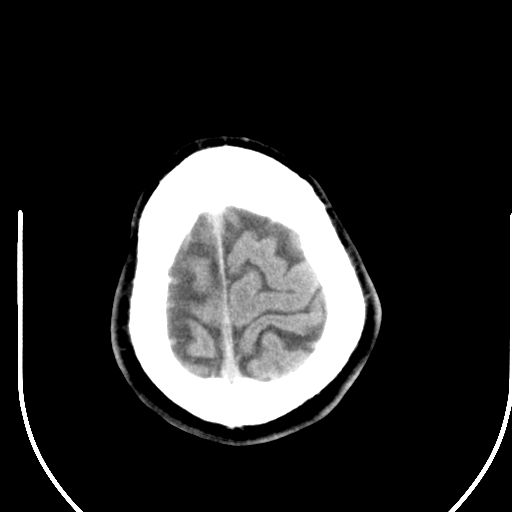

标题: CT25423:头部外伤意外发现右顶叶??? [打印本页]

标题: CT25423:头部外伤意外发现右顶叶???

ct值约13hu。

右顶叶低密度影考虑脑沟

边缘清晰,没有占位效应,不像脑沟,结合ct值,软化灶可能吧

与脑沟没关系,小软化灶或陈旧性感染吧!

看样年纪不小了直接报腔梗,当然你要想报软化灶也是一样的

考虑右侧额叶巨腔隙灶;建议必要时行mri检查。